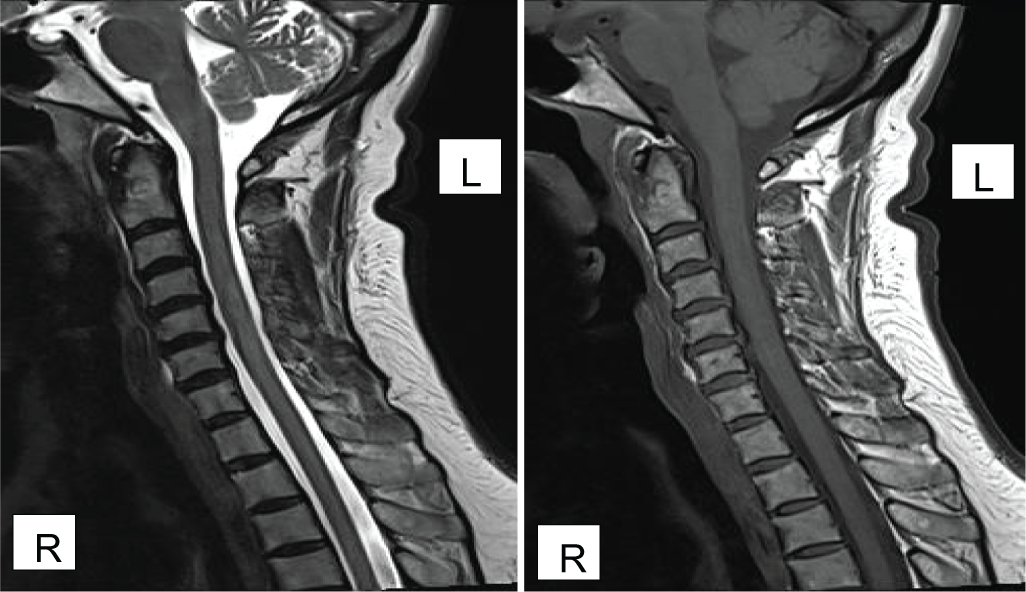

Indication Based MR Imaging: Impact on Diagnosis and Patient Management